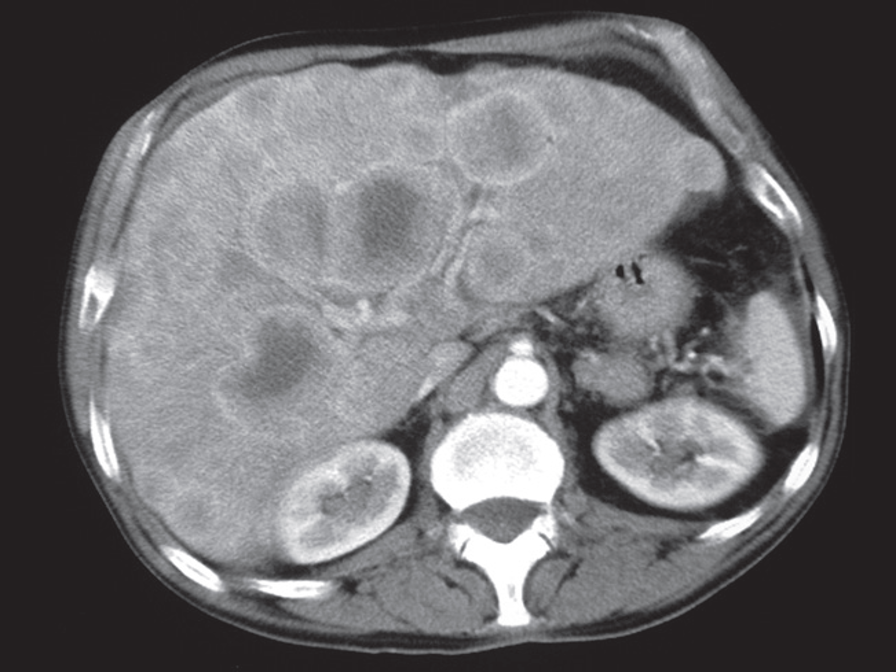

At CT, metastases are seen as rounded areas, usually lower in density than the contrast enhanced surrounding parenchyma, Most are well demarcated from the adjacent parenchyma.

CT scan of liver metastases There are a large number of low density lesions in both lobes of the liver, which show enhancement around their edges. The patient had carcinoma of the bronchus.